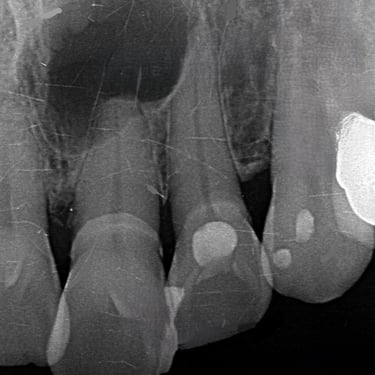

Calcificación Pulpar

La calcificación pulpar es la formación de depósitos de calcio dentro de la pulpa dental, que puede dificultar el tratamiento de conducto.

Los pacientes generalmente no tienen síntomas, pero pueden experimentar sensibilidad.

El tratamiento incluye la eliminación de los depósitos durante el tratamiento de conducto. Es importante tratarlo para evitar complicaciones durante el procedimiento.